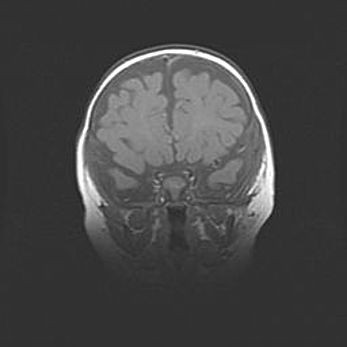

Множественные кисты обоих полушарий головного мозга, наибольшая из них в правой затылочной области. Ассиметричная атрофическая гидроцефалия.

Возраст: 7 месяцев

Вес: 5660 г

Пол: мужской

Окружность головы: 41,5 см

Срок гестации: 28-29 недель

Кисты головного мозга развиваются в результате многоочаговых некрозов вещества мозга и возникают вследствие перенесенной перинатальной инфекции, менингитов, энцефалитов, асфиксии, родовой травмы, расстройств мозгового кровообращения различного генеза. Образованию кист в веществе головного мозга плодов и новорожденных способствуют такие факторы, как высокое содержание в нем воды, недостаточная (или отсутствие) миелинизация и слабая астроглиальная реакция на повреждение.

Кисты могут сочетаться с гидроцефалией и другими поражениями головного мозга.